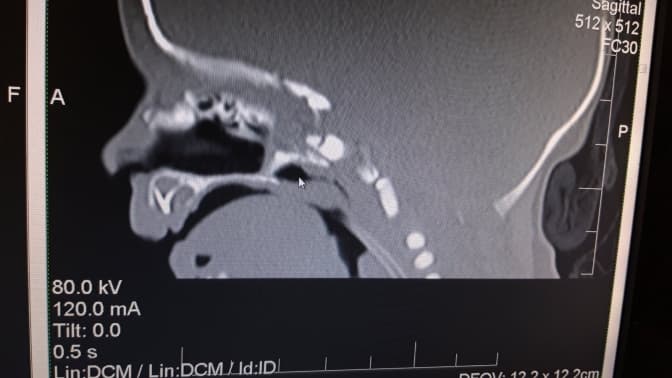

На консультацію вирішили запросити дитячих лікарів-отоларингологів, які підтвердили підозри. Патологія вимагає ургентної операції, тому після комп’ютерної томографії разом з отоларингологами почали підготовку до оперативного втручання для формування носових ходів, щоб дитина могла дихати самостійно.